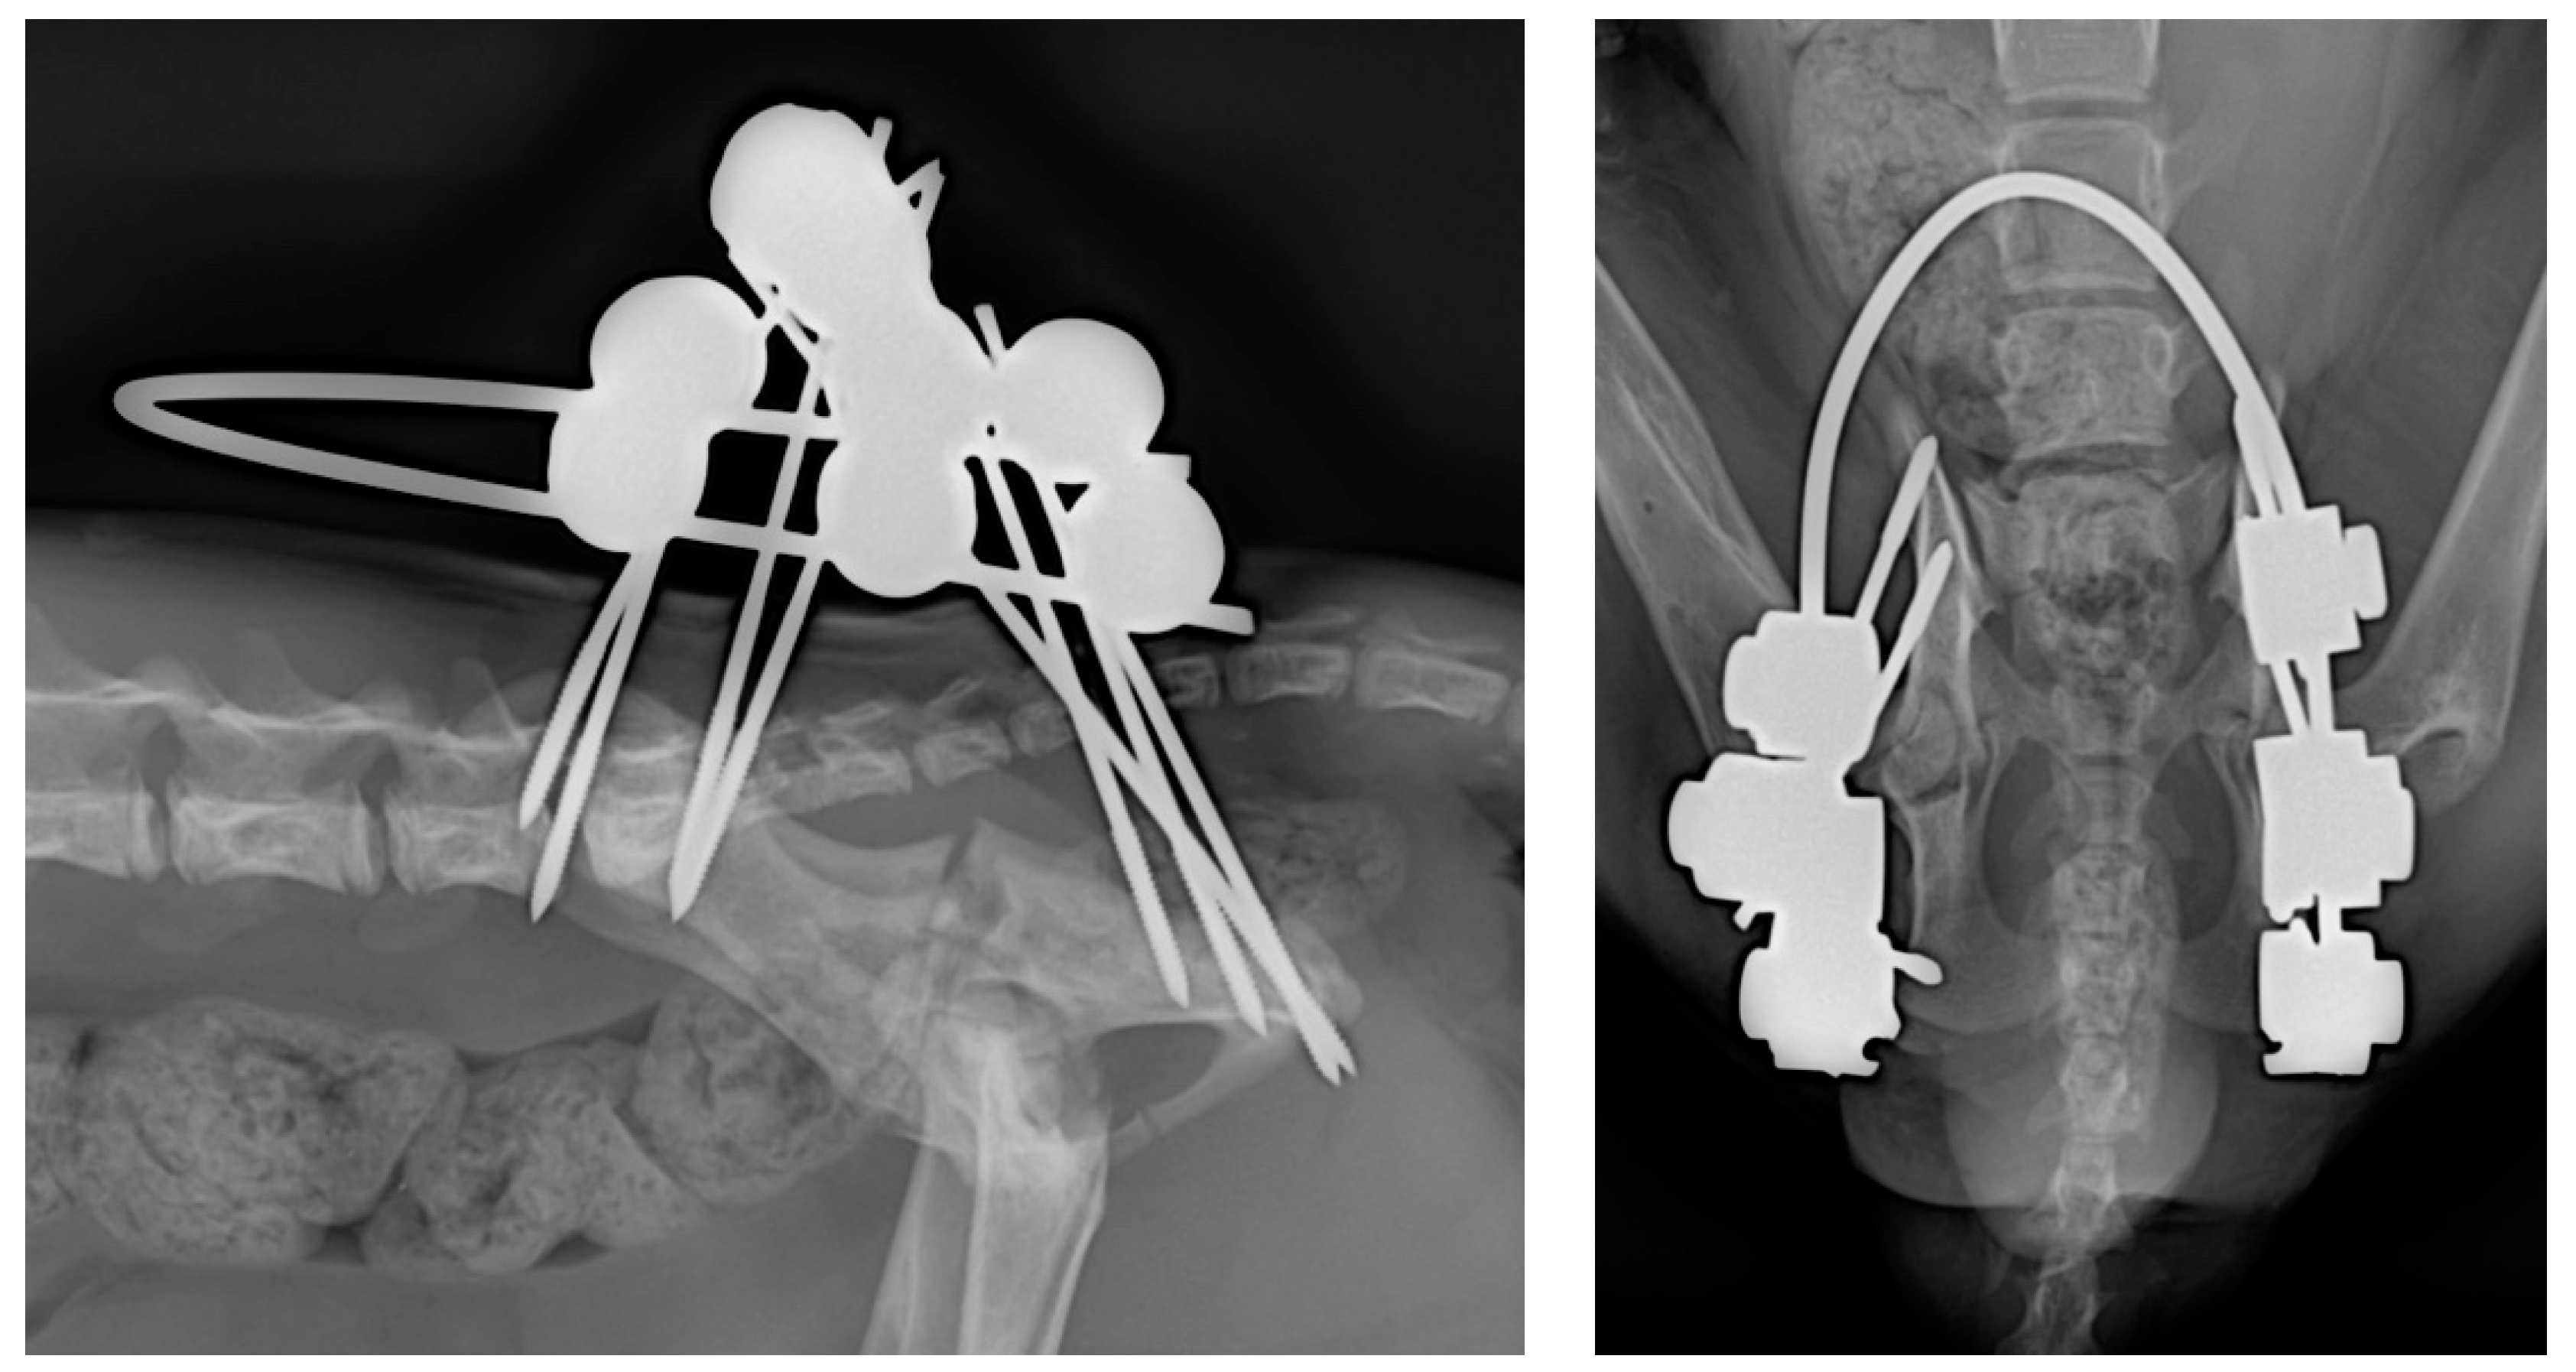

2.2. Surgical Technique

- Sacral tuberosity corridor of the ilium, near the origin of the gluteus medius muscle. The pins were inserted at an angle of 10–15° from proximo-medial to disto-lateral to the vertical.

- Corridor of the body of the ilium, in the caudal aspect, along the origin of the gluteus profundus muscle, with pins inserted at an angle of 10–15° to the vertical of the iliac crest.

- Ischial tuberosity corridor, with pins inserted at an entry angle of 10–15° to the vertical.